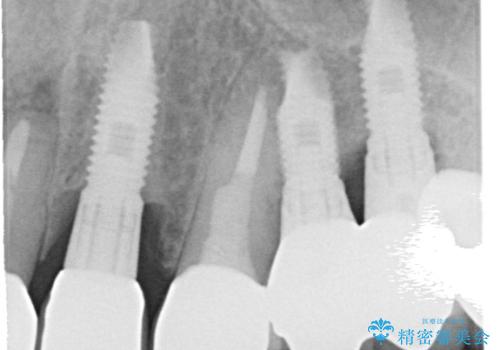

- 「被せ物が揺れている」を主訴に来院された患者様です。診査診断を行い被せ物が外れているのではなく、コアという土台ごと外れていたので、土台ごとやり変えた後オールセラミッククラウンで治療を行いました。

ファイバーコアという土台を建てるときに唾液が入ると接着に良くないのでラバーダムシートを使用しています。加えてマイクロスコープを使用しながら行う事で外れにくい土台を作ることが出来ます。その後、形成を行いシリコンで型取りしたのち、オールセラミッククラウンで修復しました。